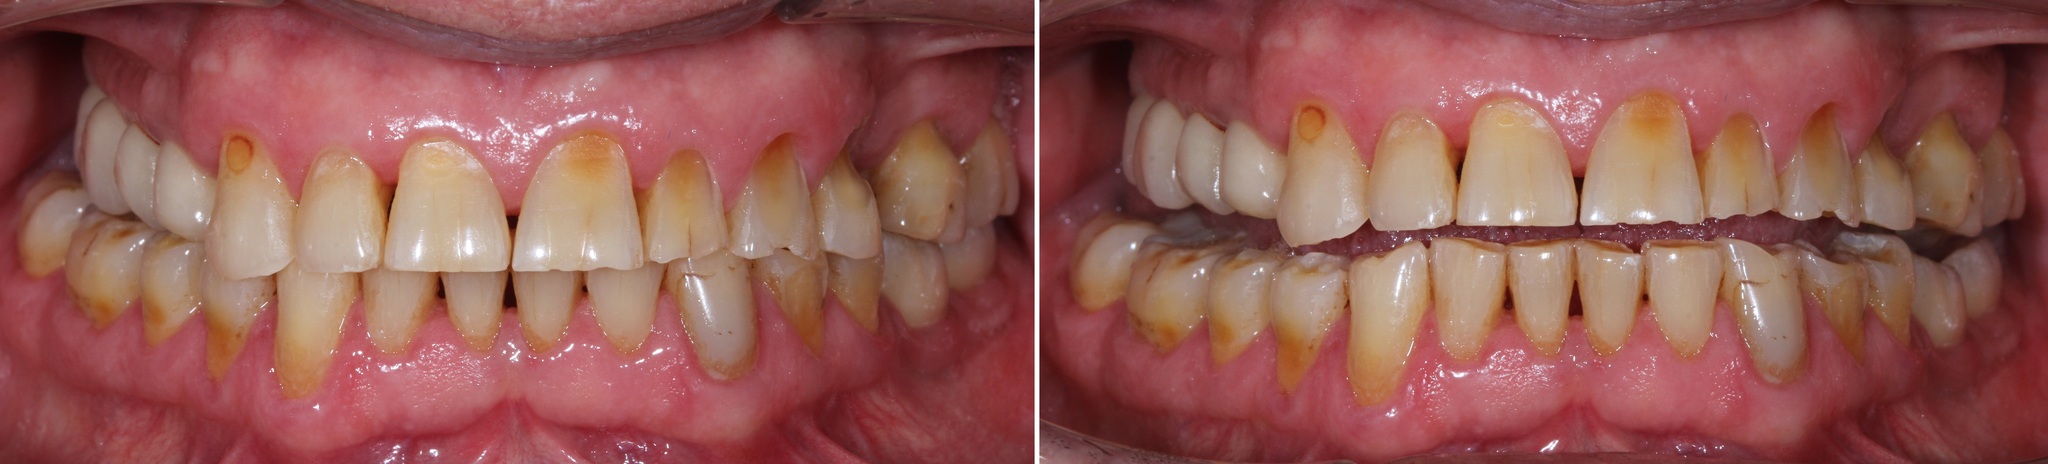

Обратите внимание, как сильно истерты зубы, а в области шеек этих зубов – клиновидные дефекты (некариозное поражение твердых тканей зубов, при которых зуб приобретает форму клина).

Основной причиной появления клиновидных дефектов является перегрузка из-за неправильного смыкания зубов.

Зубы за 3.5 года жизнь потрепала. Режущие края истерлись, появилось больше клиновидных дефектов:

Особенно не выдержал натиска времени 6й верхний левый зуб: